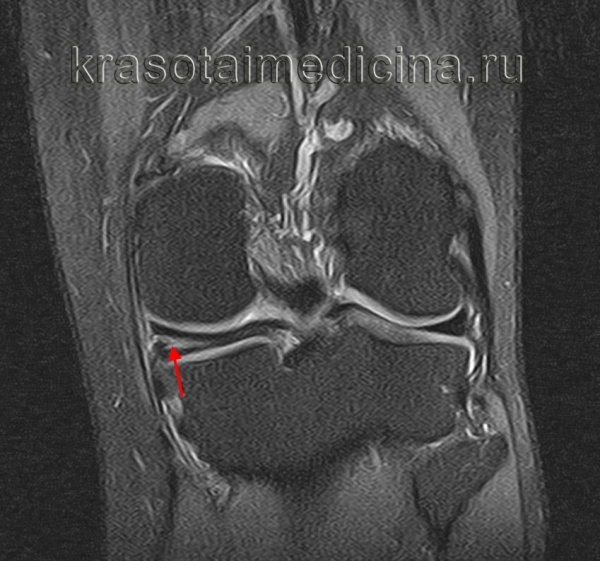

(Слева) МРТ PDВИ, сагиттальный срез: у пациента с разрывом передней крестообразной связки (ПКС) (изображение отсутствует) определяется периферический ВПР медиального мениска. Центральный фрагмент мениска достаточно крупный настолько, что мог быть ошибочно принят за целый задний рог и интерпретирован как неповрежденный.

(Справа) МРТ Т2ВИ, режим подавления сигнала от жира, сагиттальный срез: у этого же пациента определяется гиперинтенсивный сигнал от разрыва и темная ткань мениска на периферии разрыва. Периферический ВПР может быть с легкостью определяться на последовательностях чувствительных к жидкости. (Слева) MPT PDBИ, сагиттальный срез: определяется вертикальный продольный разрыв заднего отдела медиального мениска. Этот разрыв немного смещен. Небольшой периферический фрагмент мениска позволяет отличить данный разрыв от отделения мениска от капсулы.